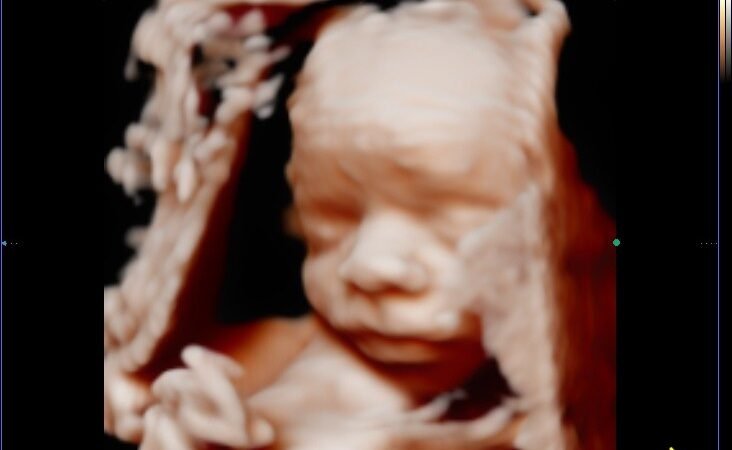

Si tuvieras que elegir un solo momento para hacer tu ecografía 5D, elige la semana 26. En esta etapa el bebé ya tiene los rasgos faciales bien definidos, hay suficiente líquido amniótico para obtener imágenes nítidas y todavía tiene espacio para moverse y cambiar de posición. El resultado son imágenes hiperrealistas con una claridad impresionante.

Podrás ver su carita completa, sus labios, su nariz, cómo mueve las manitas… Es el momento en el que las familias salen de la consulta llorando de la emoción.

El punto dulce del embarazo para la ecografía emocional. Los rasgos ya están definidos, el bebé tiene algo de grasita que redondea su carita y sigue teniendo espacio para moverse. Las imágenes de la cara son espectaculares: se puede distinguir perfectamente si tiene los labios de mamá o la nariz de papá y no parara de moverse.

En estas semanas el bebé tiene más grasita y sus mejillas están más redondeadas, lo que da un resultado muy tierno y dulce. Sigue siendo un momento muy bueno para hacer la ecografía, aunque hay algo menos de líquido amniótico que en semanas anteriores. Los primeros planos de la cara son increíbles.